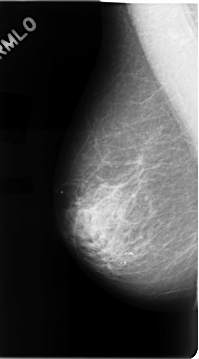

C_0050_1.LEFT_MLO

LEFT_MLO LINES 4720 PIXELS_PER_LINE 2528 BITS_PER_PIXEL 12 RESOLUTION 50 OVERLAY